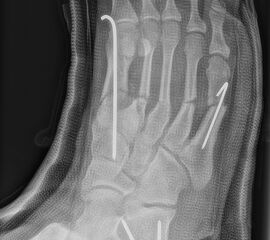

Calcaneus-Osteotomie

Die minimalinvasive Calcaneusverschiebeosteotomie bietet eindeutige Vorteile gegenüber dem offenen Verfahren, sodass wir bei Kindern und Jugendlichen nahezu keine offene Verschiebeosteotomie mehr durchführen. Am Calcaneus liegt die offene Wachstumsfuge dorsal. Bei der Durchführung müssen Schenkel der V-förmigen Osteotomie daher etwas steiler angelegt werden, in einem stumpfen Winkel (siehe Abb. 3 a-j). Für die Osteotomie liegen unsere Patienten auf dem Rücken und der BV wird für die exakte Seitaufnahme eingestellt. Der Fuß lagert auf einem hohen OP-Kissen und die Osteotomie kann bequem mit einem langen Kirschner-Draht und einem sterilen Stift angezeichnet werden (Abb. 15).

Abb. 16 a-f: Varisation einer valgischen Calcaneusstellung bei Knick-Senk-Fuß mit V-förmiger Osteotomie axiale Ansicht (a), seitliche Ansicht (b), d. p. Ansicht (c) und nach Entfernung der Drähte seitliche Ansicht (d), Caudalisierung des dorsalen Calcaneus bei iatrogenem Plattfuß nach Klumpfußüberkorrektur (e) und Cranialisierung beim Hohlfuß (f).